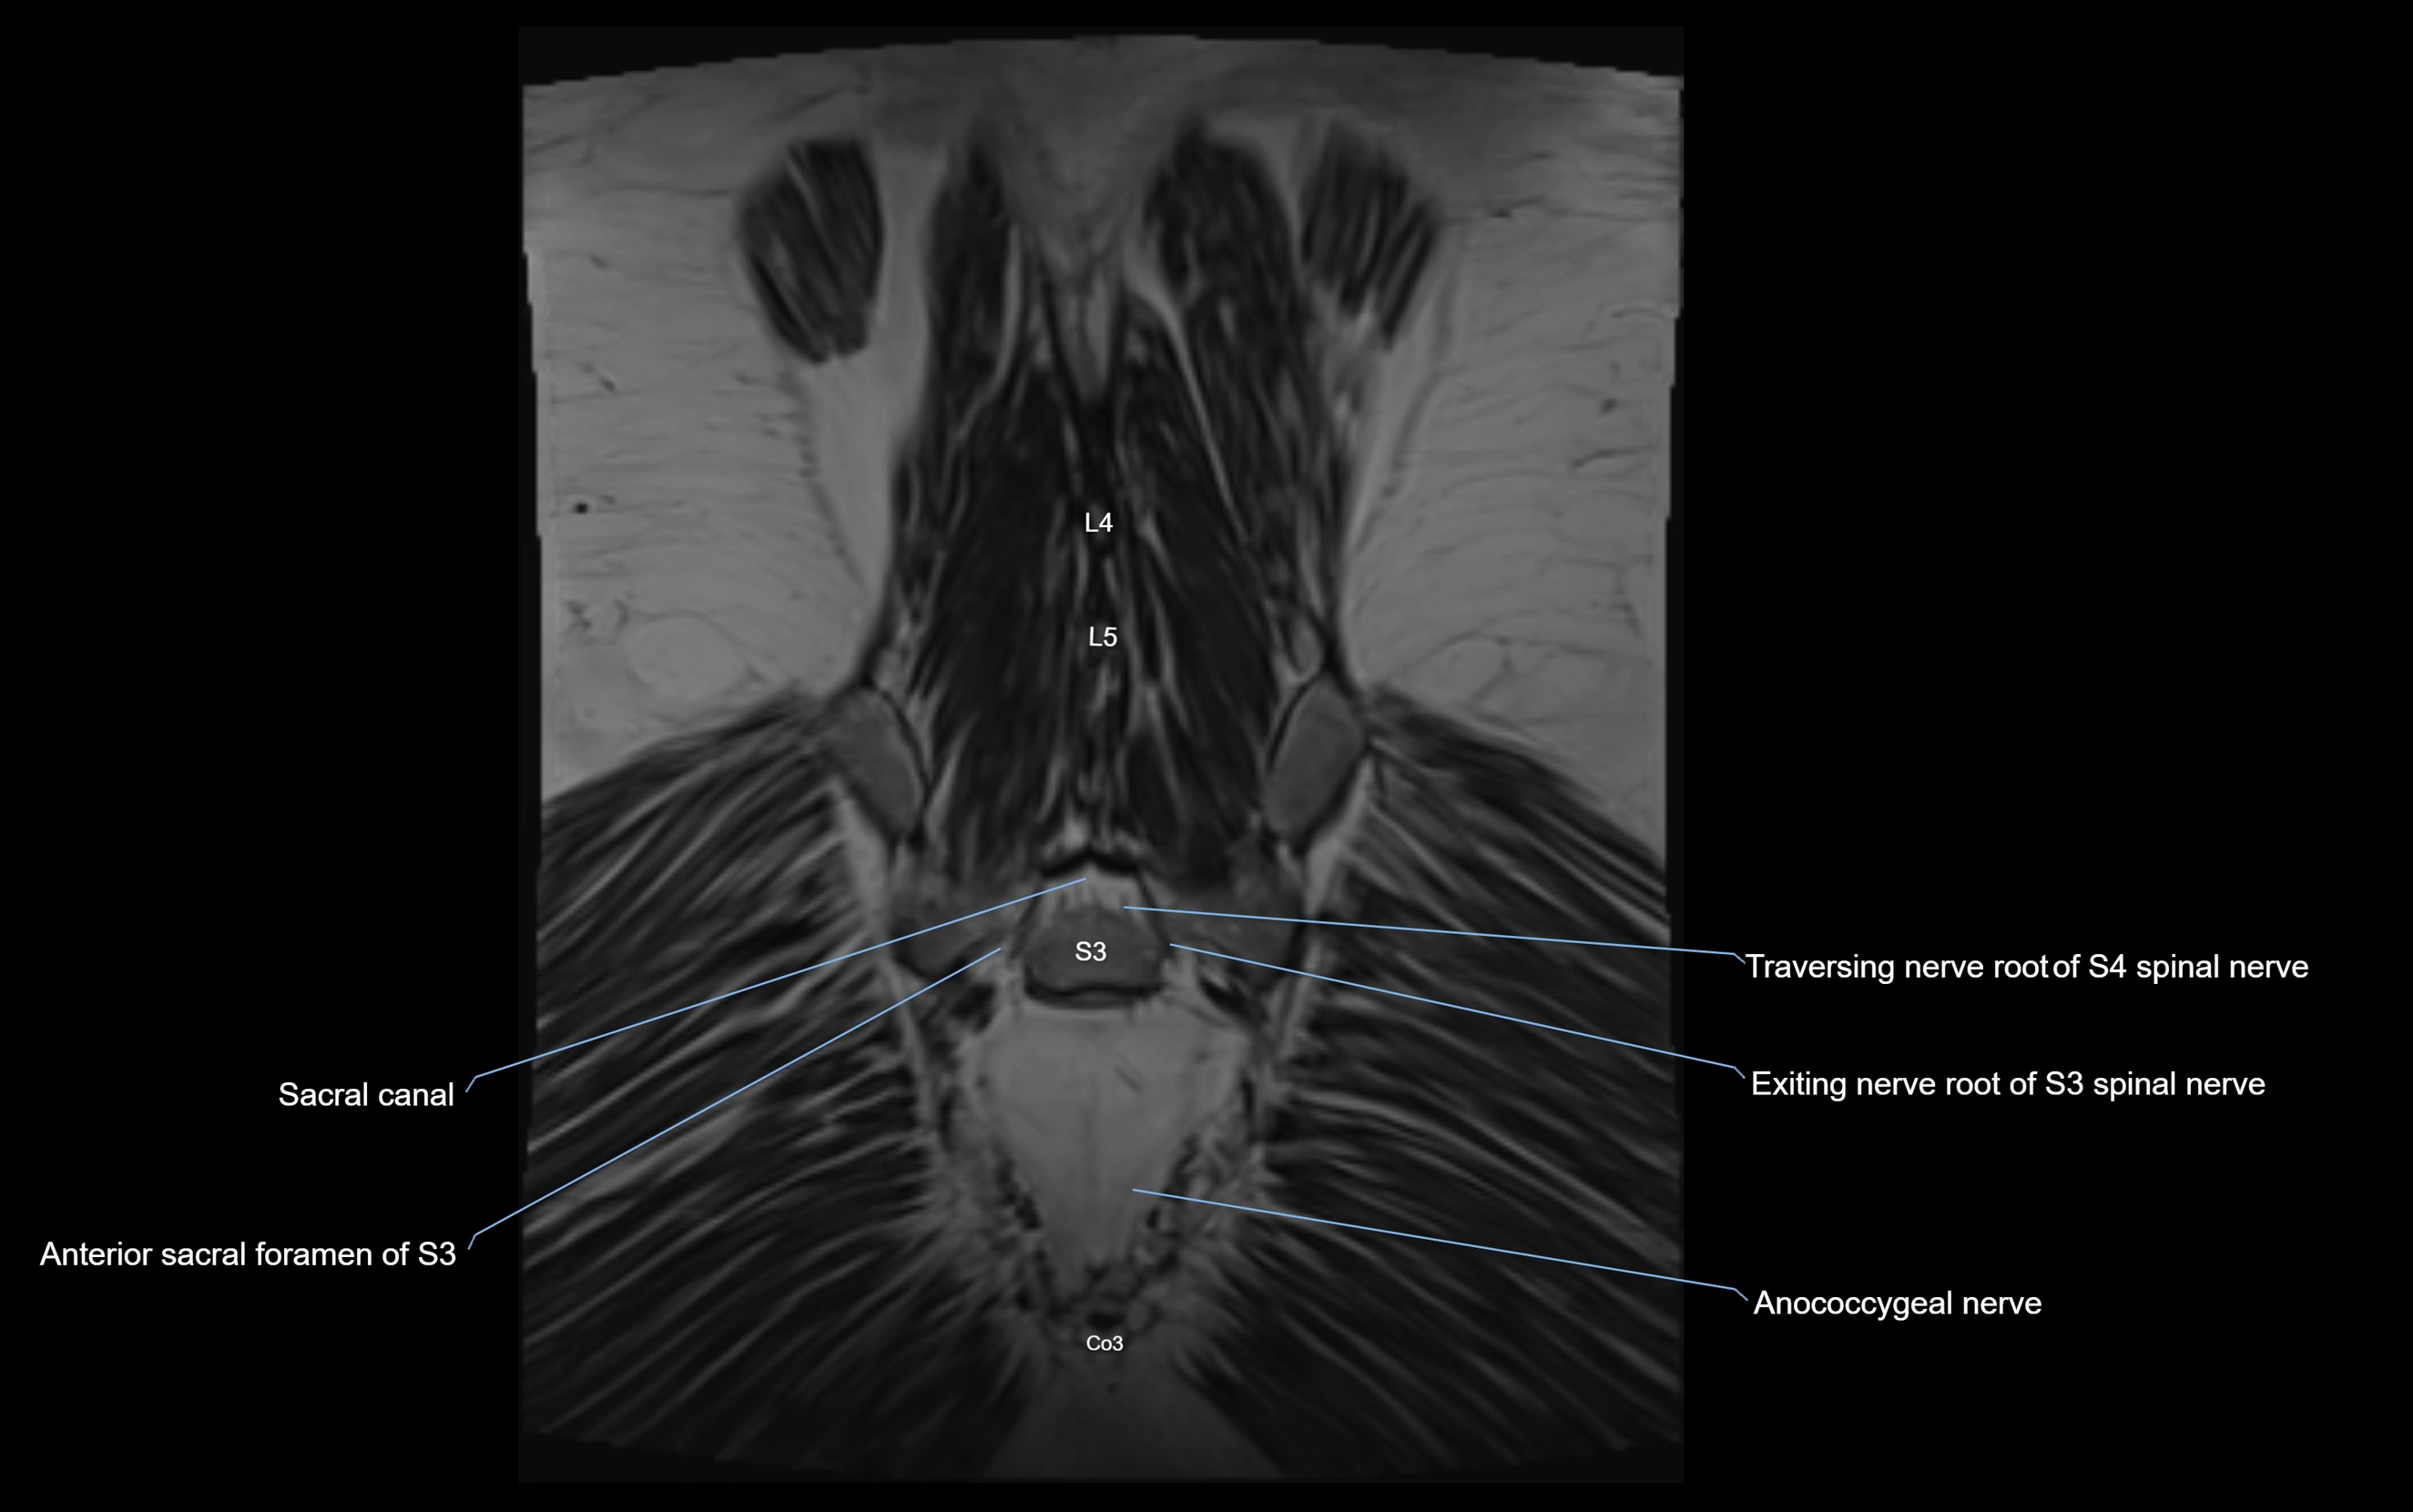

Anococcygeal nerve

The anococcygeal nerve is a small sensory nerve derived from the coccygeal plexus, which itself is formed by the ventral rami of S4, S5, and the coccygeal nerve (Co1). Although tiny, this nerve plays an important role in supplying the skin of the coccyx and the area between the anus and coccyx. It passes through the sacrotuberous ligament and runs in the midline behind the coccyx.

MRI image

image